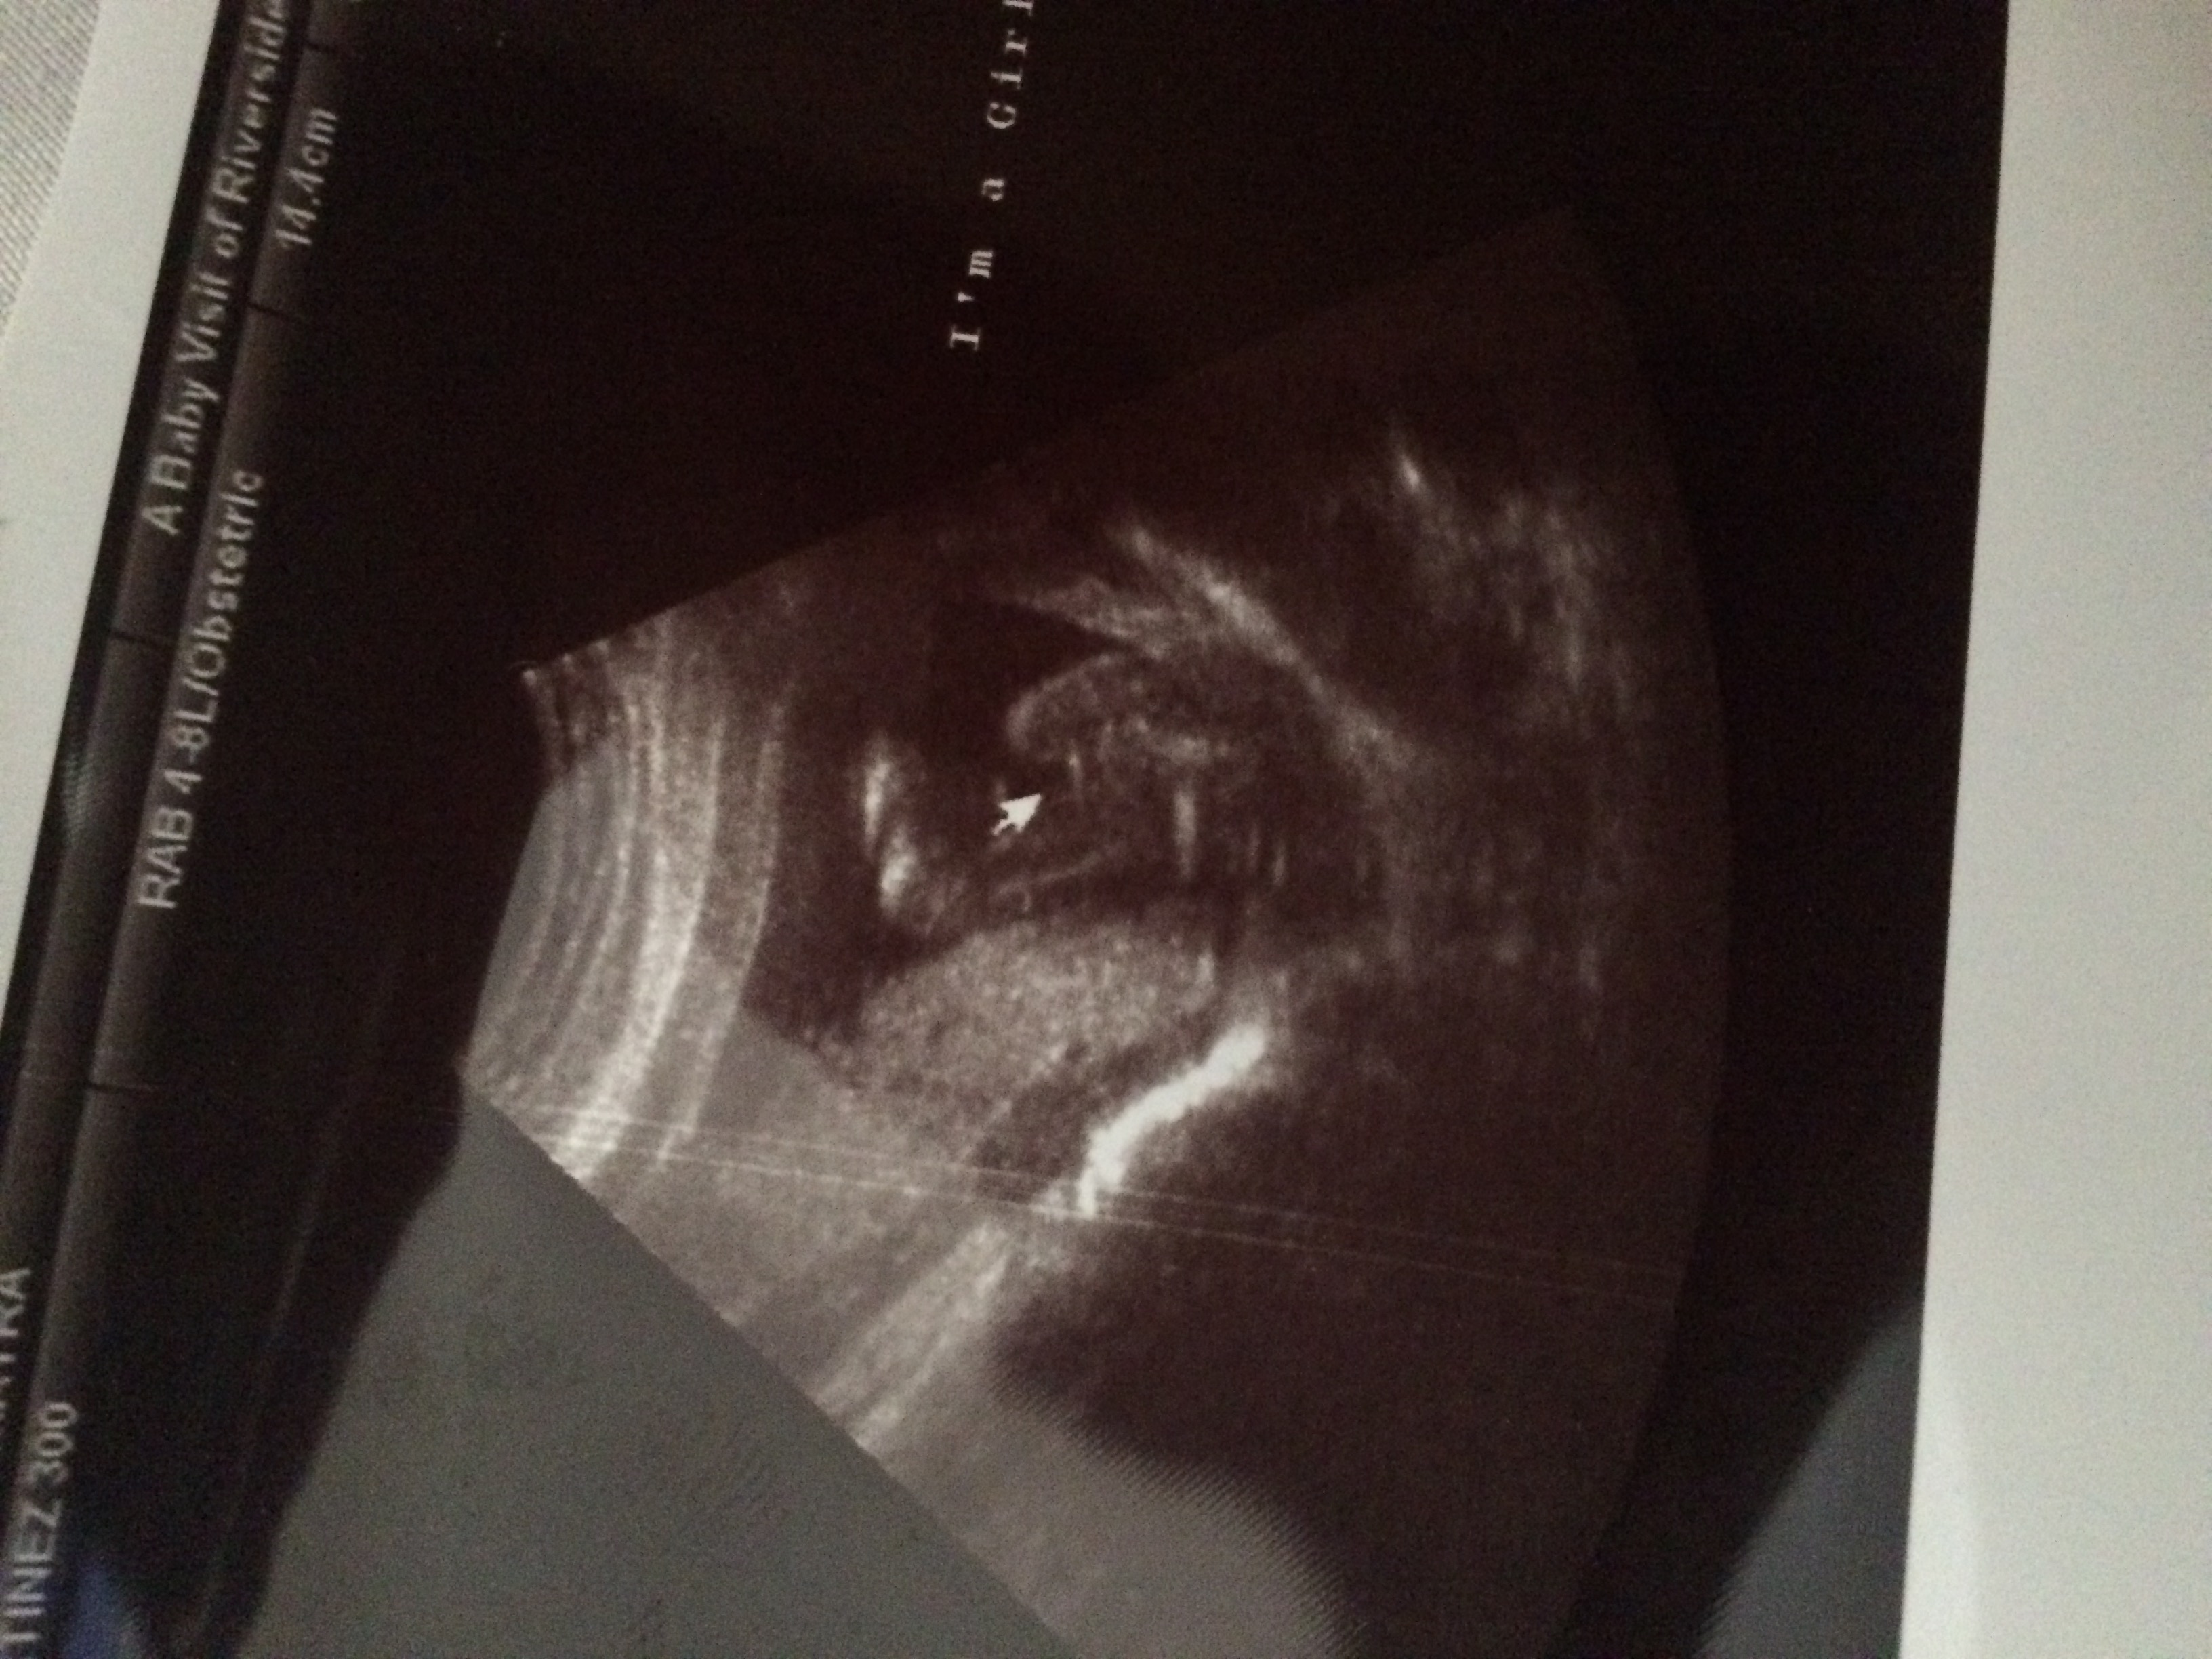

Okay so yesterday I posted to see if my baby girl was a girl but the picture I posted wasn't to good . So now here the close by picture that the tech gave me. So is my baby girl a girl 99.9%?

I'm baffled by the part where it says "i'm a girl" right on the pic. The tech IMO would not have written that unless they were very sure of the sex.